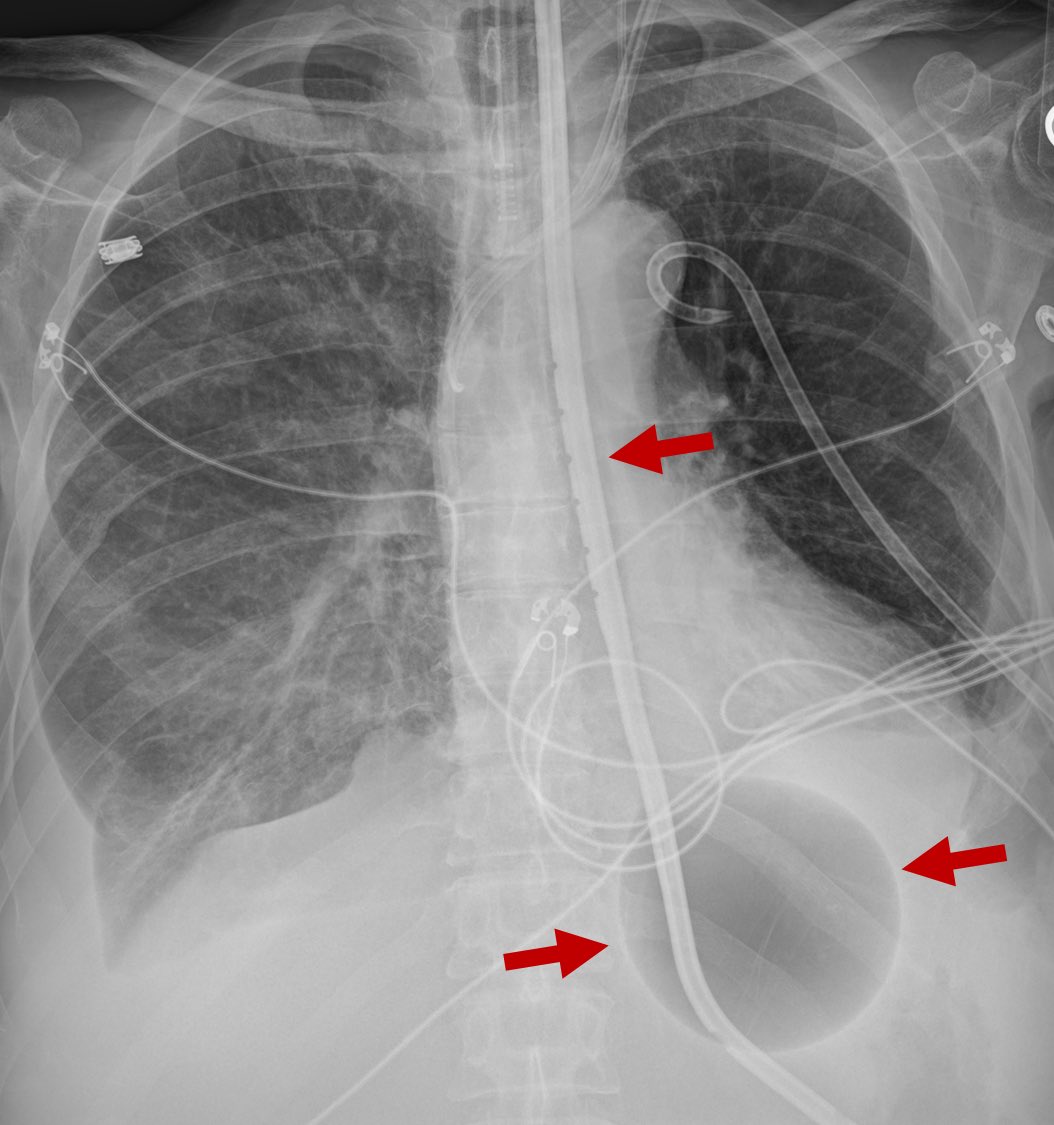

This is a blakemore tube. A sengstaken-blakemore tube. It’s used to tamponade UGI hemorrhage due to varices in emergency situations. Notice the large air bubble that’s been insufflated to tamponade those bleeders

This is a blakemore tube. A sengstaken-blakemore tube.

It’s used to tamponade UGI hemorrhage due to varices in emergency situations.

Notice the large air bubble that’s been insufflated to tamponade those bleeders